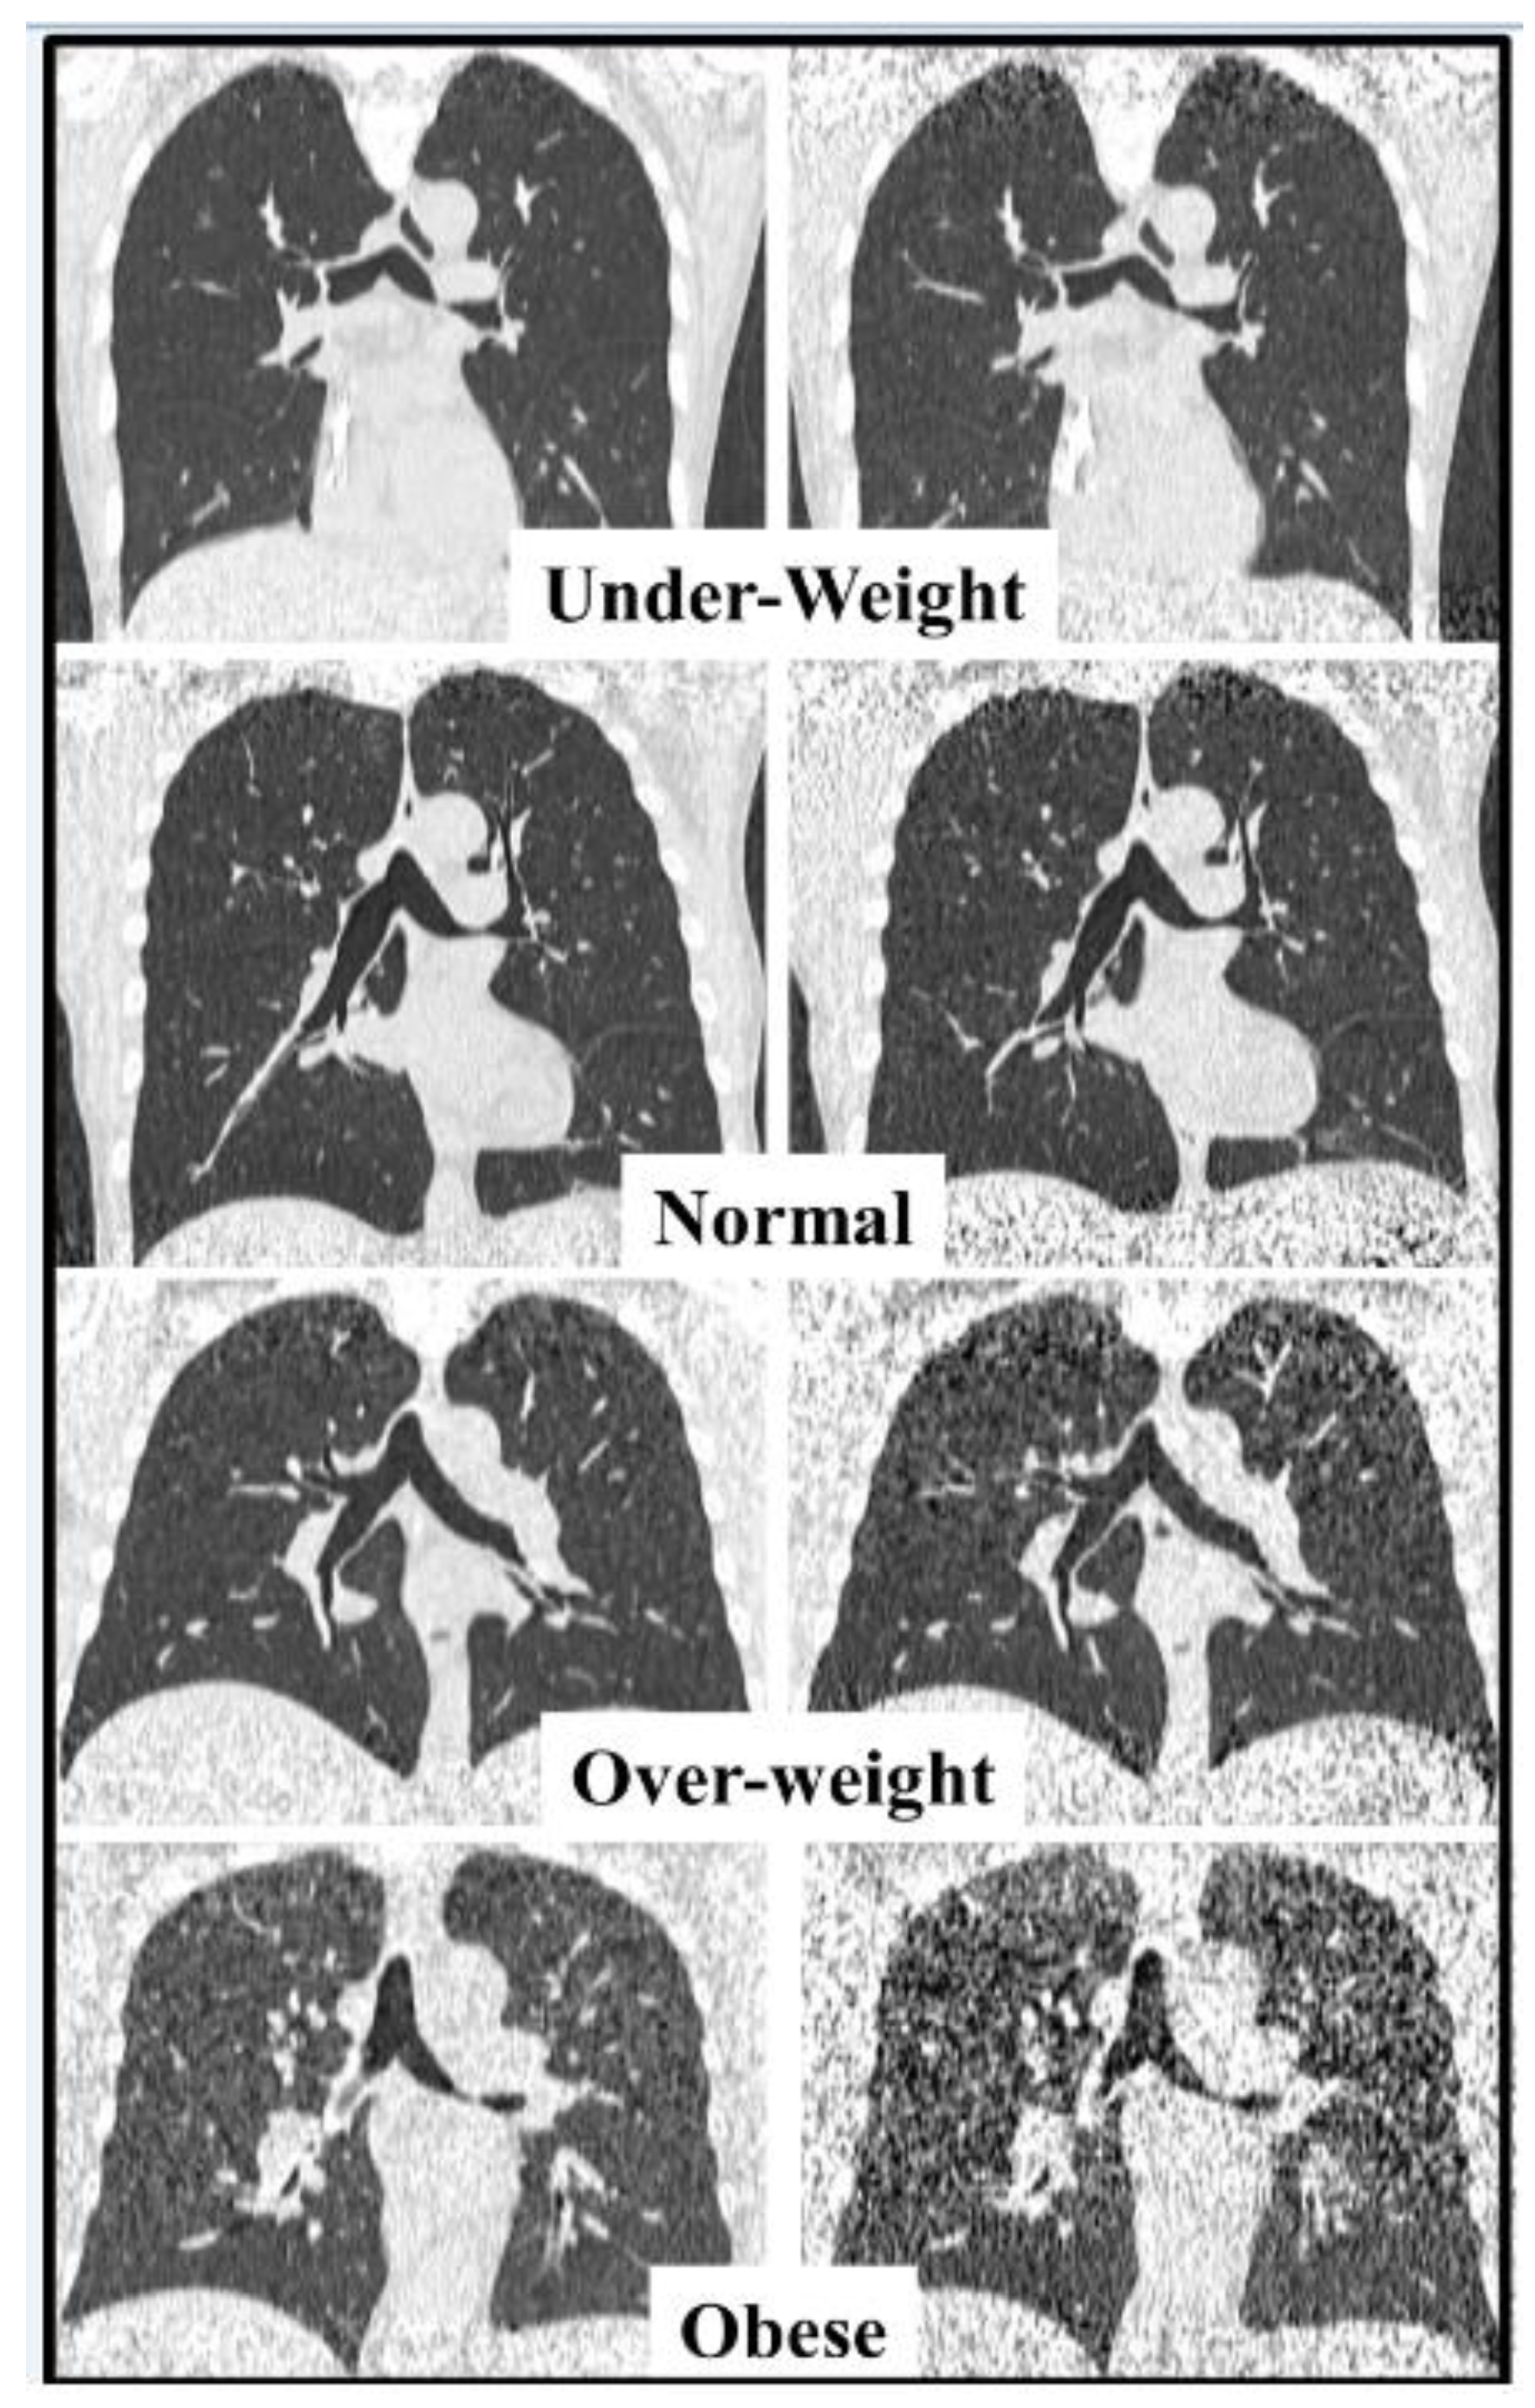

4.1. Image Quality (IQ) Assessment

| All | Underweight | Normal | Overweight | Obese | |

|---|---|---|---|---|---|

| Number of patients | 100 | 5 | 46 | 28 | 21 |

| Male/Female | 53/47 | 3/2 | 26/20 | 16/12 | 8/13 |

| Age (years) | 55.3 ± 14.7 [18–80] | 51.4 ± 18.6 [22–69] | 55.3 ± 15.8 [19–80] | 56.3 ± 13.1 [27–74] | 55.1 ± 15.0 [18–76] |

| BMI a (kg/m2) | 26.2 ± 6.3 [14.7–60.2] | 16.5 ± 1.6 [14.7–18.2] | 22.6 ± 1.4 [19.8–24.9] | 27.1 ± 1.5 [25.1–29.4] | 34.0 ± 3.8 [30.0–44.6] |

| LDCT DLP a (mGy × cm) | 125.7 ± 18.9 [85.5–160.8] | 123.8 ± 21.7 [93.9–148.5] | 123.2 ± 21.5 [85.5–158.3] | 125.2 ± 17.4 [95.7–160.8] | 132.0 ± 12.9 [100.6–150.7] |

| uLDCT DLP a (mGy × cm) | 30.5 ± 4.7 [20.6–39.1] | 30.0 ± 5.4 [22.7–36.1] | 29.9 ± 5.3 [20.6–38.5] | 30.4 ± 4.3 [23.1–39.1] | 32.1 ± 3.2 [24.3–36.7] |

| LDCT Effective a Dose (mSv) | 1.76 ± 0.26 [1.20–2.25] | 1.73 ± 0.30 [1.31–2.08] | 1.73 ± 0.30 [1.20–2.22] | 1.75 ± 0.24 [1.34–2.25] | 1.85 ± 0.18 [1.41–2.11] |

| uLDCT Effective a Dose (mSv) | 0.43 ± 0.07 [0.29–0.55] | 0.42 ± 0.08 [0.32–0.51] | 0.42 ± 0.07 [0.29–0.54] | 0.43 ± 0.06 [0.32–0.55] | 0.45 ± 0.04 [0.34–0.51] |